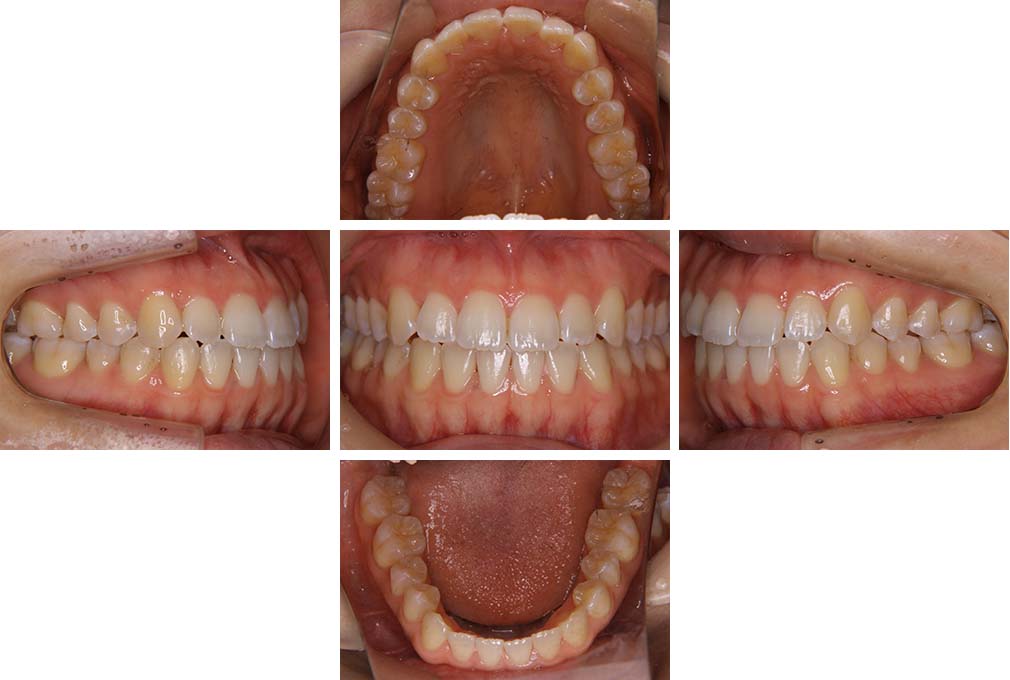

CASE:03

上下顎前突

初診時年齢 18歳4か月

性別 男性

治療費の目安 105万円程度(治療開始時)

歯列の乱れは著しくなく上顎右側側切歯が捻転し口蓋側へ転位していた。また、問診の中で患者さんから最も重視する治療結果として口元の突出の改善の申出があった。下顎が後退した上顎前突傾向ではあったが著しいものではなかった。上下顎前突と診断し上下顎小臼歯抜歯を行っていただき、上下顎舌側マルチブラケット装置を使用して、矯正用アンカースクリューを併用して動的治療を行った。上下顎前歯の後退を十分行い口元の突出感も改善した。治療後10年1か月の来院時には口元の突出感が再発することもなく、下顎前歯の少しの唇舌的なずれはあったが歯列は安定していた。動的治療期間2年2ヵ月間。

治療前

18歳4ヵ月

治療後

動的治療期間2年2カ月間

20歳10か月

10年経過

動的治療終了後10年1カ月

30歳11か月